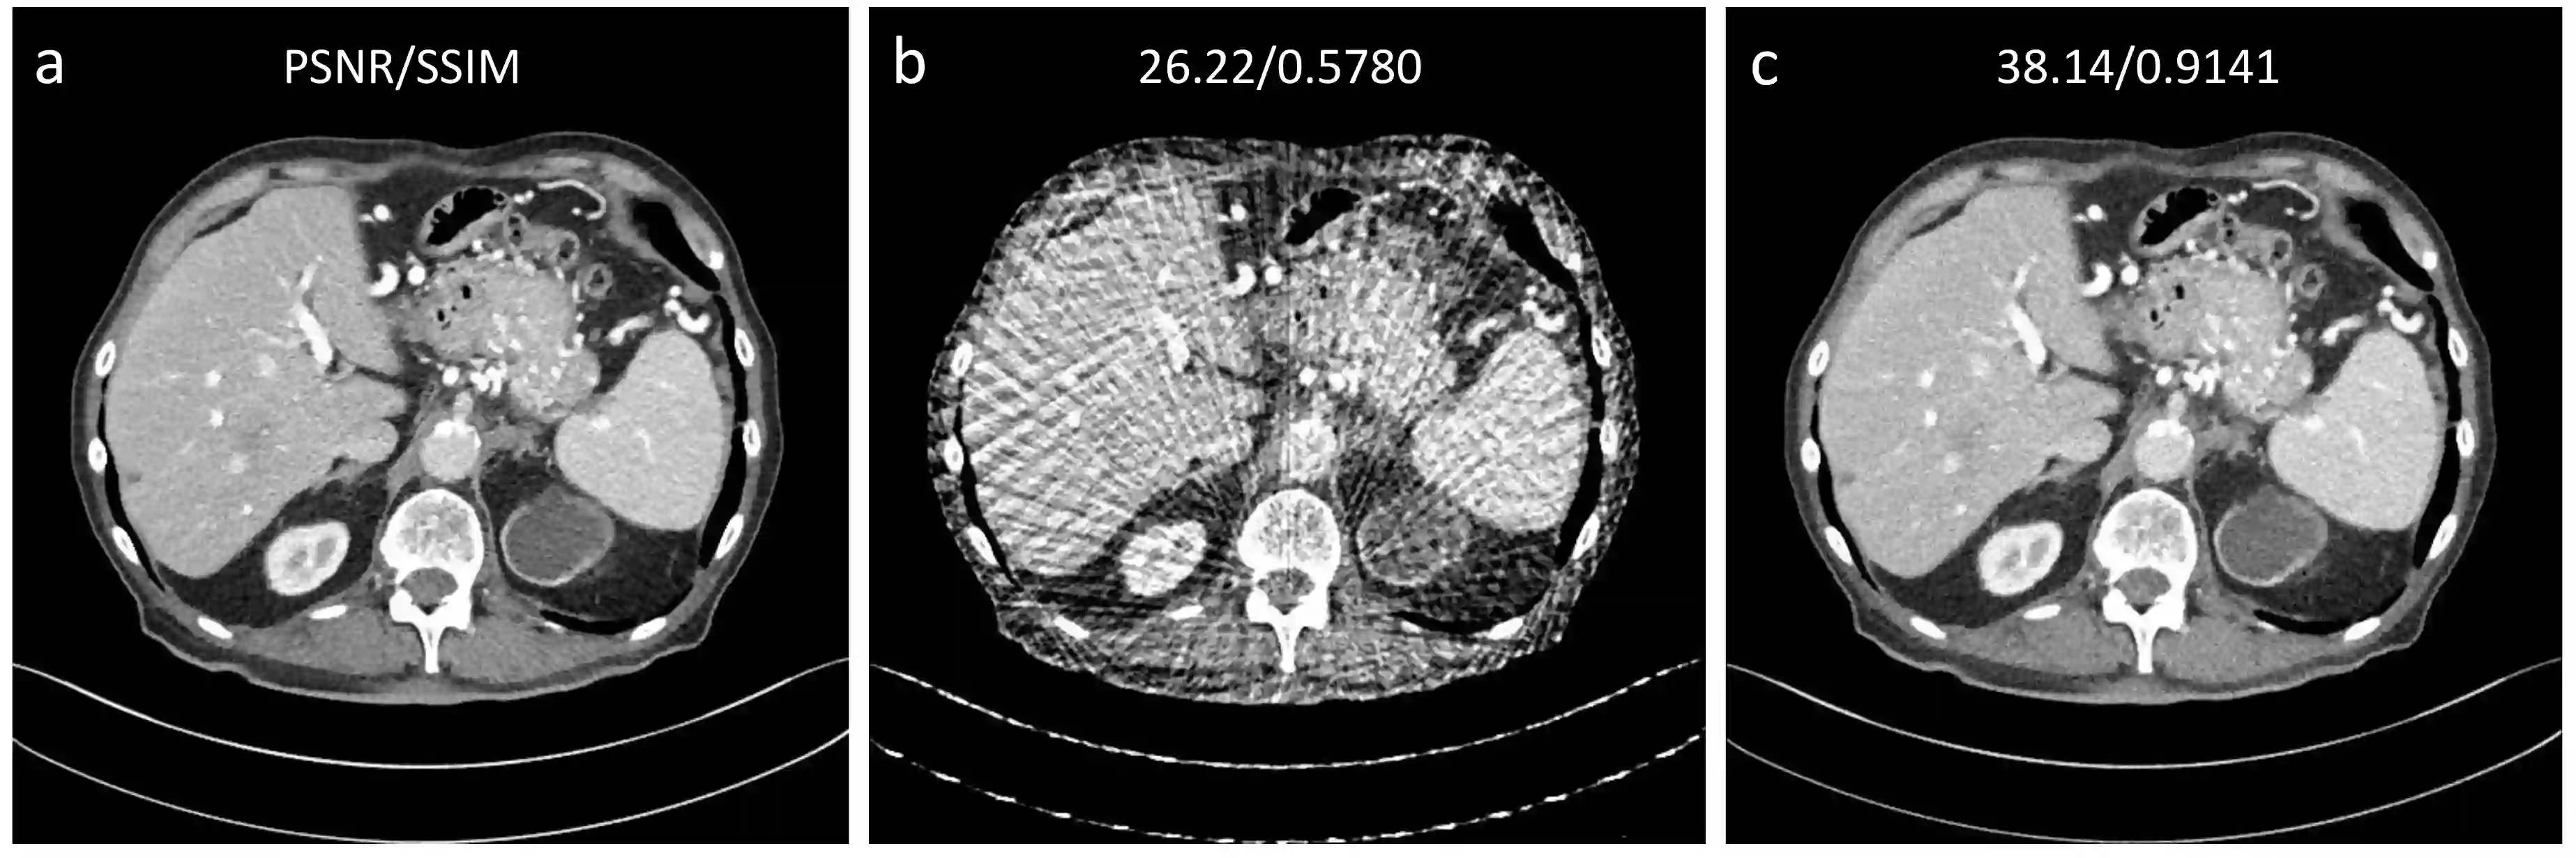

Sparse-view computed tomography (CT) can be used to reduce radiation dose greatly but is suffers from severe image artifacts. Recently, the deep learning based method for sparse-view CT reconstruction has attracted a major attention. However, neural networks often have a limited ability to remove the artifacts when they only work in the image domain. Deep learning-based sinogram processing can achieve a better anti-artifact performance, but it inevitably requires feature maps of the whole image in a video memory, which makes handling large-scale or three-dimensional (3D) images rather challenging. In this paper, we propose a patch-based denoising diffusion probabilistic model (DDPM) for sparse-view CT reconstruction. A DDPM network based on patches extracted from fully sampled projection data is trained and then used to inpaint down-sampled projection data. The network does not require paired full-sampled and down-sampled data, enabling unsupervised learning. Since the data processing is patch-based, the deep learning workflow can be distributed in parallel, overcoming the memory problem of large-scale data. Our experiments show that the proposed method can effectively suppress few-view artifacts while faithfully preserving textural details.